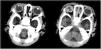

La puntuación Apgar fue de 3, 8 y 9 al minuto, los 5 minutos y los 10 minutos, respectivamente. La exploración física del recién nacido fue normal, salvo por la presencia de magulladuras en el rostro y una lesión ocular (fig. 1). A las cuatro horas de nacer, el neonato ingresó en la unidad de cuidados intensivos neonatales, donde el examen realizado por un oftalmólogo pediátrico objetivó perforación de la córnea del ojo derecho asociada a prolapso del iris e hifema. La tomografía computarizada craneal reveló la presencia de perforación ocular, un cristalino dismórfico y desprendimiento coroideo (fig. 2). Se practicó sutura de la córnea a las siete horas de vida, sin complicaciones intraoperatorias (fig. 3A). La ecografía ocular postoperatoria detectó hemorragia vítrea. Se inició tratamiento con dexametasona intravenosa, tropicamida tópica, ofloxacino, cloranfenicol y prednisolona. A las tres semanas, la córnea se mostraba más transparente, el hemovítreo se estaba reabsorbiendo y el cristalino se encontraba en la cámara anterior del ojo. A los dos meses, el paciente fue operado para extraer el cristalino y practicar una vitrectomía con objeto de resolver complicaciones de la ruptura del cristalino (fig. 3B).

(A) Apariencia de la córnea del ojo derecho tras la cirugía. Hifema visible a pesar del edema difuso de la córnea. La flecha indica la localización de la sutura en la córnea. (B) Tras la extracción del cristalino: mayor transparencia de la córnea, fibrosis residual secundario a traumatismo (flecha blanca) y burbuja de aire en la cámara anterior del ojo al final de la cirugía (flecha negra).